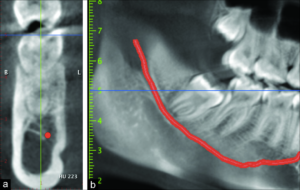

الوقاية تبدأ بالتشخيص المبكر. باستخدام الأشعة المقطعية وليست الاشعه السينيه فقط ، يمكن للطبيب تحديد مدى قرب الجذر من العصب. إذا كان العصب قريبًا جدًا، يمكن اتخاذ تدابير خاصة لتجنب الضغط عليه أو جرحه أثناء الحشو أو الخلع.